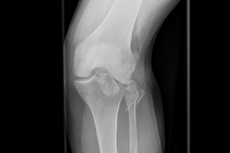

Kniegelenks-Verletzungen

Die Basisversorgung von Frakturen, die arthroskopische Chirurgie und die Fraktur-Endoprothetik, einschließlich des Teilersatzes des angrenzenden Oberschenkelknochens, gehören zum Repertoire der Klinik. So ist es uns möglich, über die Spezialisierung der Standorte unserer Klinik auch komplexeste Knieverletzungen auf höchstem Niveau zu versorgen.